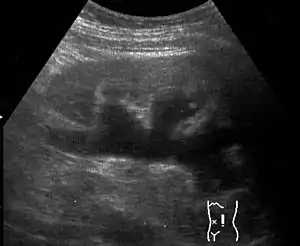

| Renal ultrasonography of hydronephrosis caused by a left ureteral stone.] | |

Massive hydronephrosis as marked by the arrow.- Renal ultrasonography of hydronephrosis[14]